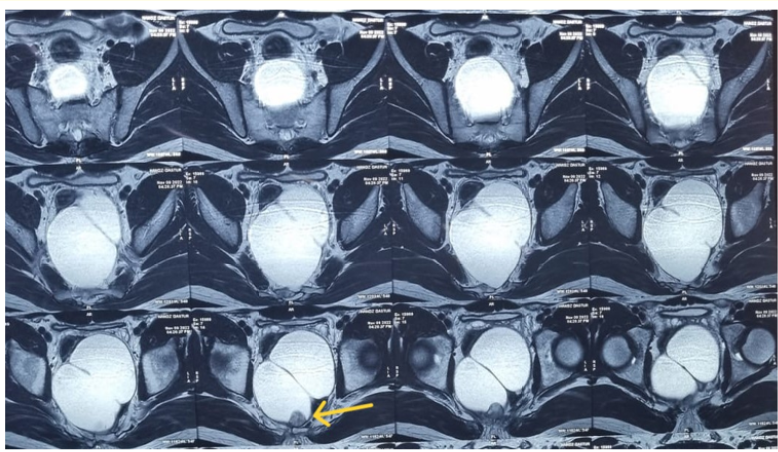

Tailgut Cyst with a Neuroendocrine Tumour

Kaiomarz Balsara, Khojasteh Dastoor, Asif Gazi and Shailee Prabhu. 10(4): 12-15.